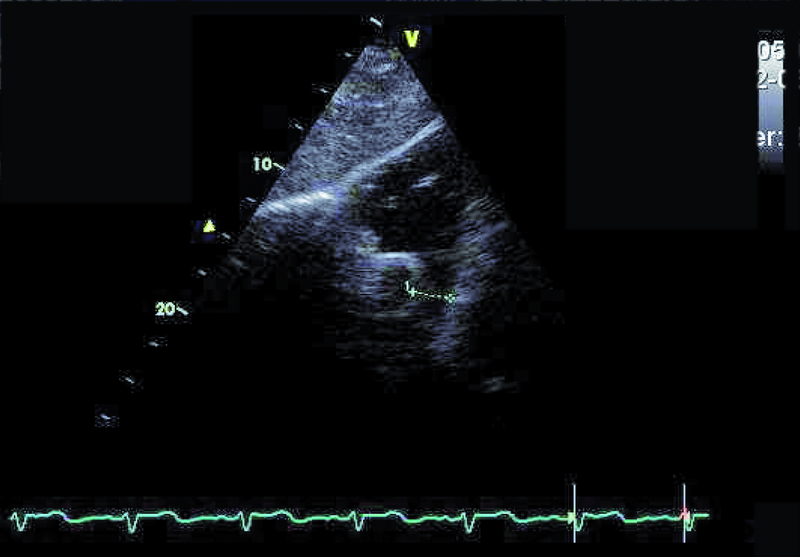

Przedstawiona chora, prawie dorosła kobieta, znajduje się w tej drugiej grupie. Jamy serca są u niej niepowiększone, a mięsień ma prawidłową grubość (ryc. 1). Rozpoznanie membrany w jamie lewego przedsionka z prawidłowym obrazem zastawki mitralnej nie nastręcza trudności. Membranę można dostrzec w wielu projekcjach (ryc. 2-4). Badanie przezprzełykowe pozwala na bardziej precyzyjne określenie średnicy otworu, która zazwyczaj waha się od kilku milimetrów do centymetra. W omawianym przypadku otwór jest duży i na podstawie samej jego wielkości można przypuszczać, że nie powoduje obstrukcji przepływu (membrana w projekcji na rycinie 4 znajduje się powyżej zastawki). Tryb doplera ciągłego (ryc. 5) także nie potwierdza zaburzeń przepływu i trudno się spodziewać, by w takiej sytuacji mogło dojść do podwyższenia ciśnienia w żyłach płucnych, włośniczkach i pniu płucnym. Średnica pnia płucnego (21 mm, ryc. 6) jest dowodem na panujące w nim niskie ciśnienie (nie zarejestrowano w badaniu fali zwrotnej trójdzielnej). Serce trójprzedsionkowe z niskim gradientem śródprzedsionkowym przy braku dodatkowych nieprawidłowości (np. przecieku międzyprzedsionkowego lewo-prawego bądź prawo-lewego – zależnie, z jaką jamą ubytek się komunikuje) nie wymaga leczenia operacyjnego. Pacjentka wymaga dalszej kontroli, ponieważ po wielu latach choroby mogą pojawić się napadowe lub utrwalone nadkomorowe zaburzenia rytmu serca, będące wyrazem zmiany geometrii przedsionka.